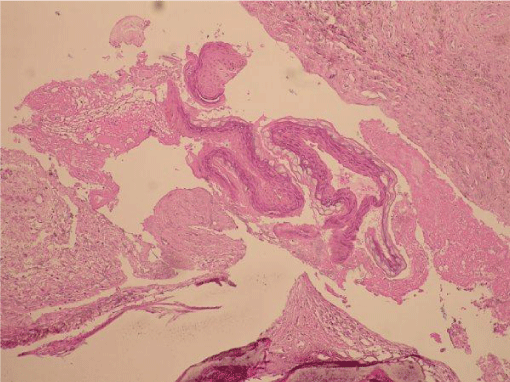

The surgical specimen was submitted for histopathological examination; in its microscopic description, loose fibroconective tissue was identified, with ducts of dilated salivary glands, and in the interior myxoid aspect material without cover epithelium, establishing the diagnosis of antralpseudocyst (Figure 6).

Figure 6: Histopathology of the case showing fibrous connective tissue and the absence of the epithelium.